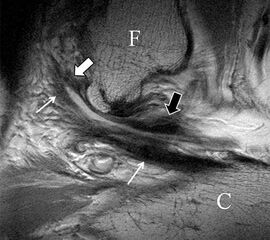

Die Definition der Dehiszenz und Lage möglicher Banddislokationen mit gelenkinterponierenden oder nach lateral umgeschlagenen Bandanteilen (Abb. 6 a und b) oder Darstellung knöcherner Ausrisse (Abb. 7), leisten einen wichtigen Beitrag zur weiteren Therapieplanung. Auch assoziierte Verletzungen der Kapsel sind normalerweise klar abgrenzbar (Abb. 6 c). Im Rahmen reparativer Prozesse und als Ausdruck einer persistierenden Stressreaktion entwickeln sich häufig synoviale oder fibrotische Meniskoide. Auch diese sind in hochauflösender Technik, ohne die Durchführung einer direkten MR-Angiographie, nachweisbar und in ihrer Ausdehnung klar zu dokumentieren (Abb. 8).

Ein diagnostisches Problem stellen nicht dislozierte Avulsionen talar- oder fibulaseitig dar, da diese eine scheinbare Bandkontinuität vortäuschen können. Selbst geringe osteo-ligamentäre Dehiszenzen lassen sich jedoch in der hochauflösenden MRT multiplanar dokumentieren und somit die Diagnose einer nicht dislozierten Avulsion mit hoher Sicherheit stellen (Abb. 4 a und b). Als weitere Alternative sind die Anfertigung schräg sagittaler Schichtführungen entlang der Längsachse des LFTA möglich, die die osteo-ligamentäre Übergänge klar visualisieren (Abb. 5). Problematisch bleibt jedoch die Differenzierung einer kompletten LFTA-Ruptur vom interstitiellen Typ mit erhaltener Kontinuität zu einer Partialruptur mit diffuser, fibrillierender Bandauftreibung.